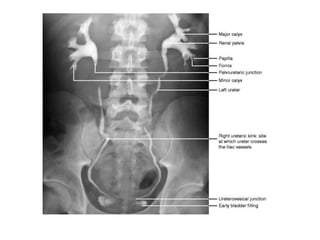

• Pyelogram (contrast in calyces) is seen 2

minutes.

• Concentrated as much as 50 times producing

a dense pyelogram.

• Plain X-ray KUB /Scout film

• 5 minute film shows nephrogram, renal pelvis,

upper part of ureter. Compression band is now

• 15 minute film: Visualisation of ureter is better in

• 35 minute film: It gives complete overview of the

urinary tract ; kidney, ureter, bladder. Bladder

• Post void film: Taken immediately after voiding. It

is used to assess

• 1. Residual urine

• 2. Bladder mucosal lesions

• 3. Diverticula

• 4. Bladder tumour

• 5. Outlet obstruction

• 6. VUR.